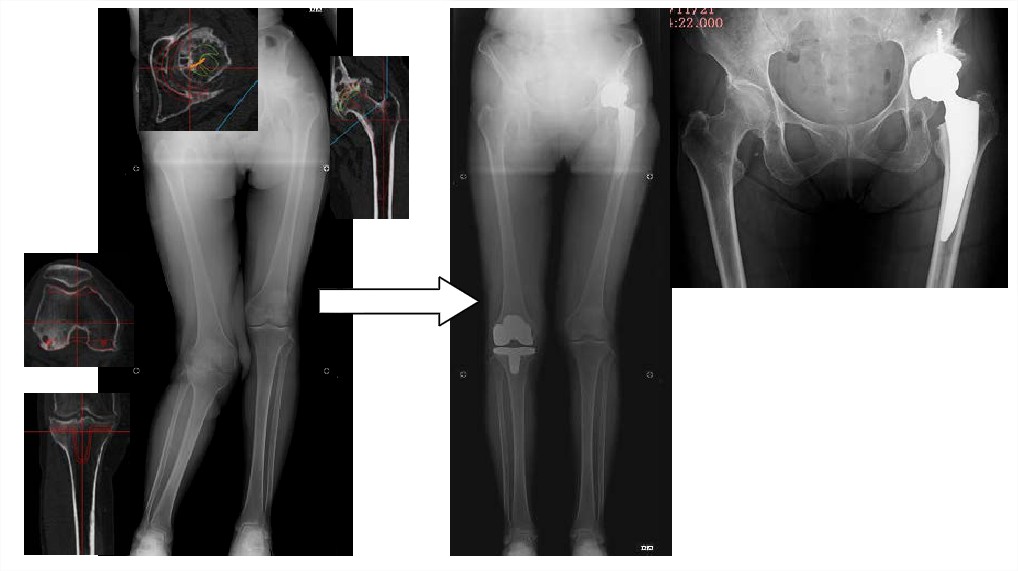

症例1

症例2

- 臼蓋側インプラント合致率は91%、大腿骨側合致率は59%であった。

- 術前から骨棘や骨嚢胞のサイズや位置まで3Dで視認でき、より正確に把握できる。

- ZedHipによる術前計画は、安心して手術に臨む一助となり得るツールである。

- シミュレーションどおりにインプラントする難易度はある。

- 一般病院で使用する術前計画手法として、より現実的な方法となりうる。